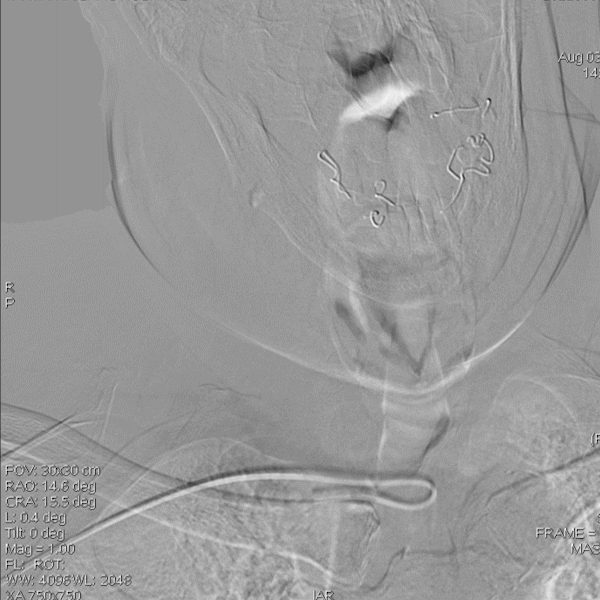

右椎动脉动脉正侧位:

导丝怎么扩【载药时代 球扩天下】NOVA DES®颅内药物洗脱支架在椎动脉颅内段重度狭窄的应用二例_https://www.jmylbn.com_新闻资讯_第29张

诊断

主要诊断:

1.右侧椎动脉V4段重度狭窄(90%);

2.高血压病2级 高危;

3.小脑梗死。